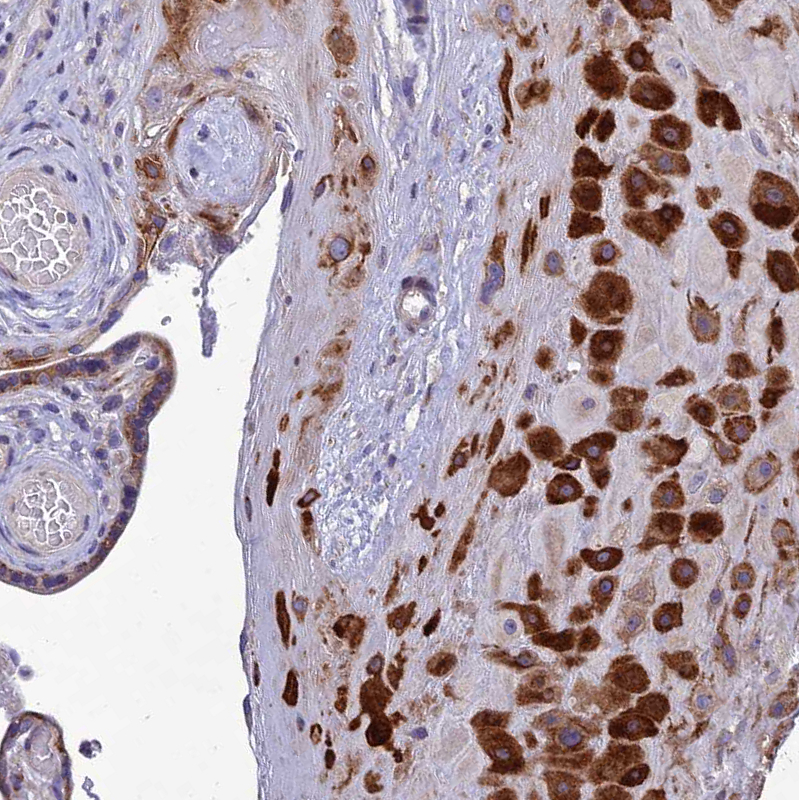

Immunohistochemical staining of human Placenta shows strong cytoplasmic positivity in decidual cells.